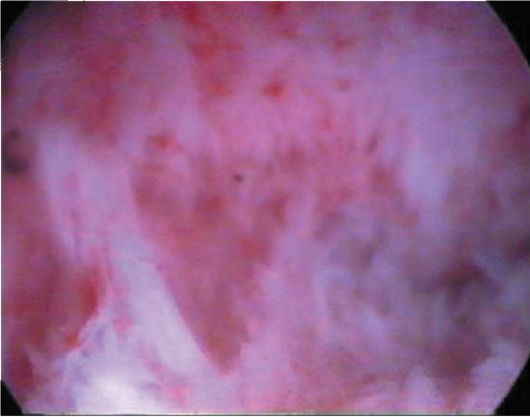

Фото. Как выглядят спайки?